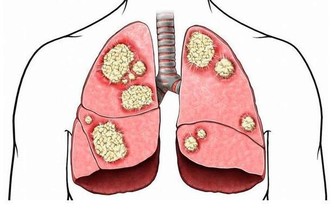

◎   胰臟癌:容易被延誤的癌症胰臟,在上腹部後腹腔,它的主要功能是分泌消化液幫助消化食物,及製造胰島素調節血糖,

由於它深藏在腹腔較後位置,因此一旦產生病變,並不容易發現。

加上胰臟癌早期無明顯症狀,等到發現時多已晚期,且症狀常與其他消化系統疾病如腹痛等混淆,建議有不明腹痛、黃疸、體重減輕現象時,應立即至肝膽腸胃科檢查。